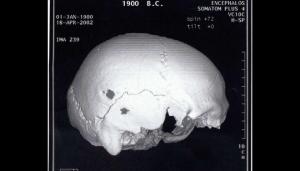

Οι Έλληνες ειδικοί, εξέτασαν το κρανίο σε αξονικό τομογράφο για να μελετήσουν τη δομή του οστού όπου είχε γίνει η επέμβαση. Η οπή είχε σχήμα ωοειδές με διαστάσεις 8 επί 7,5 χιλιοστά και τα άκρα της ήταν κυρτωμένα, υποδεικνύοντας ότι η διαδικασία της επούλωσης είχε ξεκινήσει μετά την επέμβαση.

Ήταν σίγουρα μια πολύωρη επέμβαση και επώδυνη για τον ασθενή, παρά την κατάσταση μέθης που βρισκόταν. Η μορφολογία του σχήματος της οπής, κάνει τους ειδικούς να πιστεύουν ότι η επέμβαση πραγματοποιήθηκε τρίβοντας πάνω στο κρανίο κάποιο λίθινο, κατά πάσα πιθανότητα, εργαλείο.